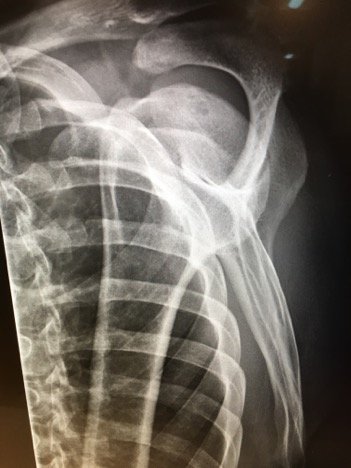

Plain films of the left shoulder showed elevation of the left clavicle above the acromion. There was an increase in the acromioclavicular (AC) and coracoclavicular (CC) distances (increased joint distances marked with red and blue arrows, respectively). A normal AC joint measures 1-3 mm whereas a normal CC distance measures 11-13 mm.1 The injury was classified as a Rockwood type III AC joint separation.

Initial evaluation with imaging includes plain films with three views: the anterior-posterior (AP) view with the shoulder in internal and external rotation as well as an axillary, or scapula-Y view (sensitivity 40%, specificity 90% for all films).6,7 AC joint injuries are classified by the Rockwood system.8 Type I involves a sprain or incomplete tear of the AC ligaments with an intact CC ligament. The AC joint appears normal on X-ray, but can become widened with stress, achieved by having the patient hold a 10-15 pound weight from each forearm.1,9 Type II injuries involve a torn AC ligament, disrupting the AC joint. The AC joint appears widened on radiographs.1,9 The AC and CC ligaments are disrupted in type III injuries with an increased CC distance of 25%-100% on plain films.1,10 In addition to torn AC and CC ligaments, the clavicle is posteriorly displaced in a type IV injury. Because the AP film may not reveal the posterior displacement of the clavicle, the axillary view is vital for correct classification of type IV injuries.1 A type V injury involves disruption of the AC and CC ligaments as well as torn muscle attachments of the trapezius and deltoid on the clavicle and scapula, leading to greater AC joint displacement on radiographs. The CC distance appears 100%-300% greater than normal.1,10 Type VI injuries are caused by a direct blow to the superior surface of the clavicle resulting in inferior displacement. On X-ray, the lateral end of the clavicle is inferior to the acromion and coracoid processes in Type VI injuries.1